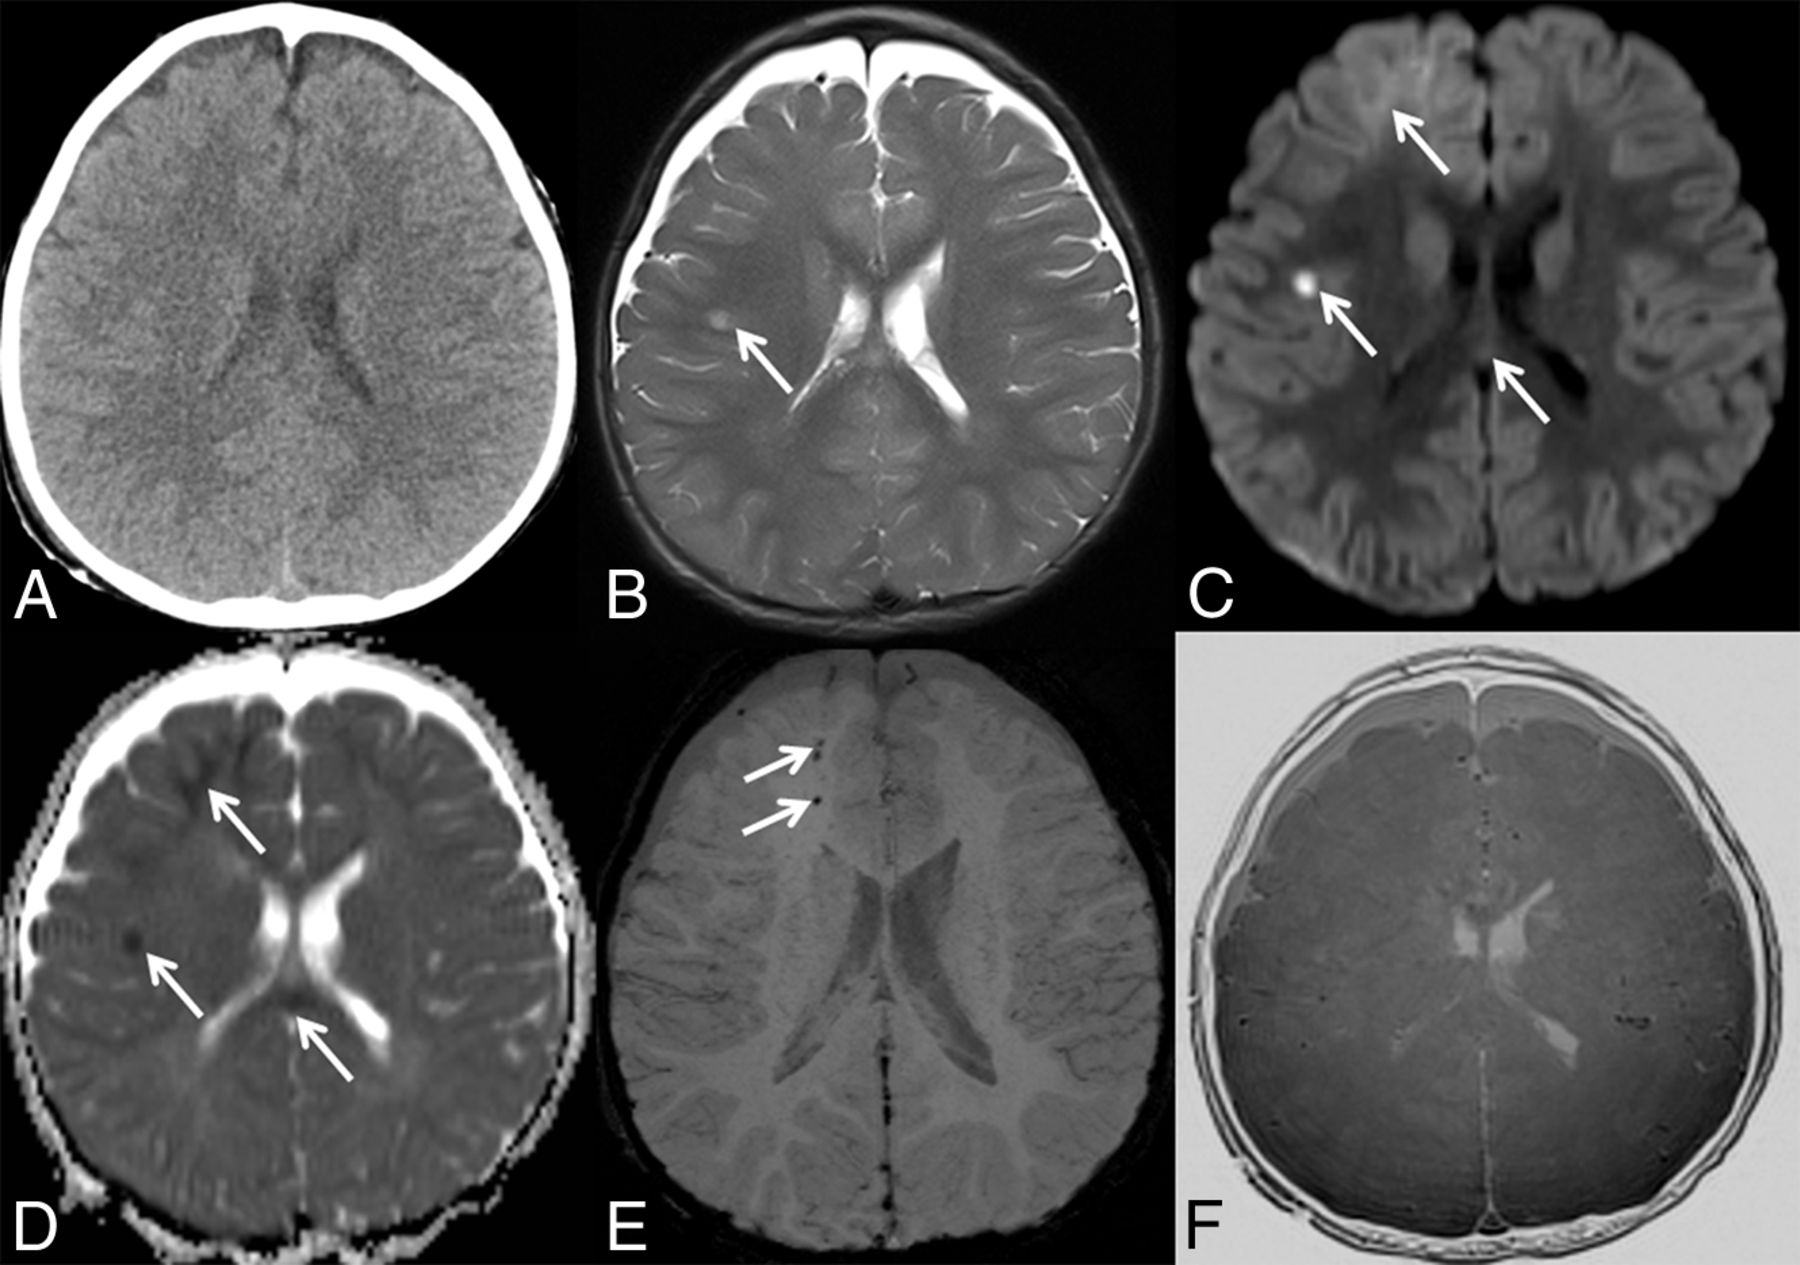

By using MR imaging including the black bone sequence as a primary screening tool in patients with neurotrauma, the number of CT studies in the pediatric population can be decreased. The identification of intracranial hemorrhages, on the other hand, has important implications for acute management and long-term outcome of children with head trauma.3,4,19 Our study reveals a higher sensitivity (100% versus 72.7%) and specificity (100% versus 83.3%) of MR imaging including black bone sequence compared with head CT in detecting intracranial hemorrhages in children with head trauma (Fig 3). The higher sensitivity and specificity of MR imaging is not surprising: The superior contrast resolution of MR imaging compared with CT results in a higher sensitivity for parenchymal lesions.20 The implementation of SWI as part of the MR imaging protocol for children with head trauma further increases the sensitivity for detection of intracranial hemorrhages. Additionally, a strong correlation has been shown between the number and volume of SWI lesions and the severity of injury (determined by the initial Glasgow Coma Scale score and the duration of the coma) as well as neurologic outcome 6–12 months after the injury.21 These results emphasize the importance of MR imaging in the acute work-up of children with head trauma. In our opinion, MR imaging as a nonionizing imaging technique should not only be an important alternative to CT in the acute evaluation of pediatric head trauma but also gradually become the main neuroimaging technique for the evaluation of traumatic skull and brain injury in the pediatric population. Specifically, the combination of highly sensitive MR imaging sequences for identification of intracranial and intra-axial lesions with a relatively sensitive MR image for clinically relevant fractures offers a diagnostically important “one-stop shopping” imaging approach. In our institution, we currently use a fast trauma head MR imaging, which combines the black bone MR image with 3D T1-weighted, axial HASTE T2-weighted, axial DWI, and SWI sequences.

A, Axial CT image does not show intracranial hemorrhage. A matching axial T2-weighted MR image (B), axial trace of diffusion (C), ADC map (D), minimal intensity projection–SWI (E), and inverted black bone MR image (F) reveal areas of T2-hyperintense signal and restricted diffusion within the temporal white matter (arrows in B–D), areas of restricted diffusion within the right frontal lobe and splenium of the corpus callosum (arrows in C and D), and foci of hypointense SWI signal within the right frontal white matter (arrows in E), suggestive of intracranial hemorrhages and diffuse axonal injury not seen on axial CT.